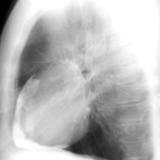

Case 1 PA

Peric calcification